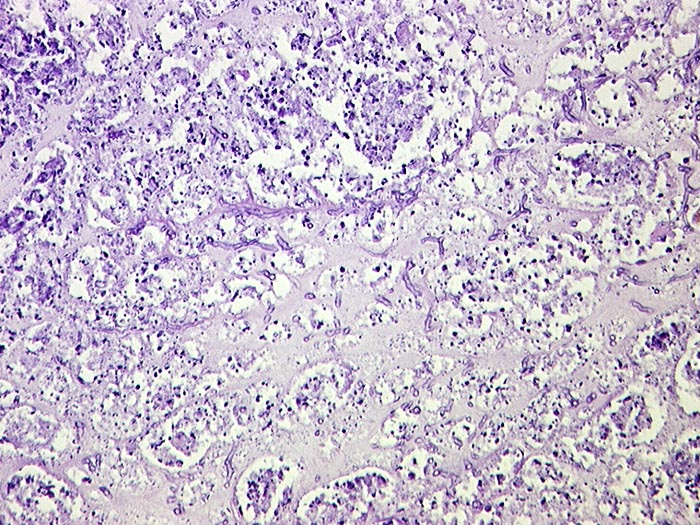

PathoPic ID 717 - Septisch embolische Nephritis: Aspergillussepsis

Septisch embolische Nephritis: Aspergillussepsis

Nekroseherd im Nierenmark durchsetzt von Aspergillusmyzelien.

Septische Herde in Haut, Nieren und Herz

Chronische lymphatische Leukämie. St.n. Chemotherapie. Steroiddauertherapie.